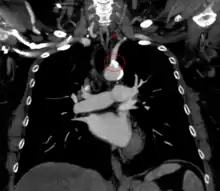

| The proximal part of left subclavian is blocked on left side so no flow in vertebral and to left arm. Blood from right vertebral enters left vertebral and flows back to supply left arm | |